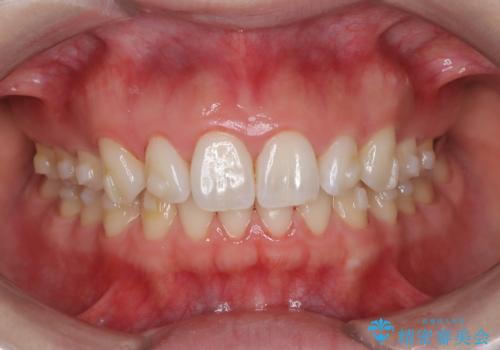

抜歯矯正をインビザラインで実現

- 患者様は、上下顎の歯列不正と前歯部の突出感を主訴としてご来院されました。診断の結果、上顎左右第一小臼歯を抜歯することでスペースを確保し、歯列全体を整える方針としました。本来はワイヤー矯正が推奨されるケースですが、患者様のご希望により、透明なマウスピース型矯正装置「インビザライン」を使用した治療計画を立案しました。治療期間は約3年で、奥歯の噛み合わせを維持しながら、徐々に前歯の位置を整えました。

インビザラインは見た目の目立ちにくさと取り外しが可能な点がメリットですが、複雑なケースでは治療計画の精密さが求められます。本症例では奥歯の噛み合わせが崩れないよう注意を払いながら、マウスピースの交換タイミングを細かく設定しました。患者様には装着時間を守っていただくことが重要で、1日20時間以上の装着が必須です。また、抜歯部位のスペースを閉じる過程で、歯の動きが停滞しやすい時期もあるため、定期的なチェックを通じて治療が順調に進むよう管理しました。